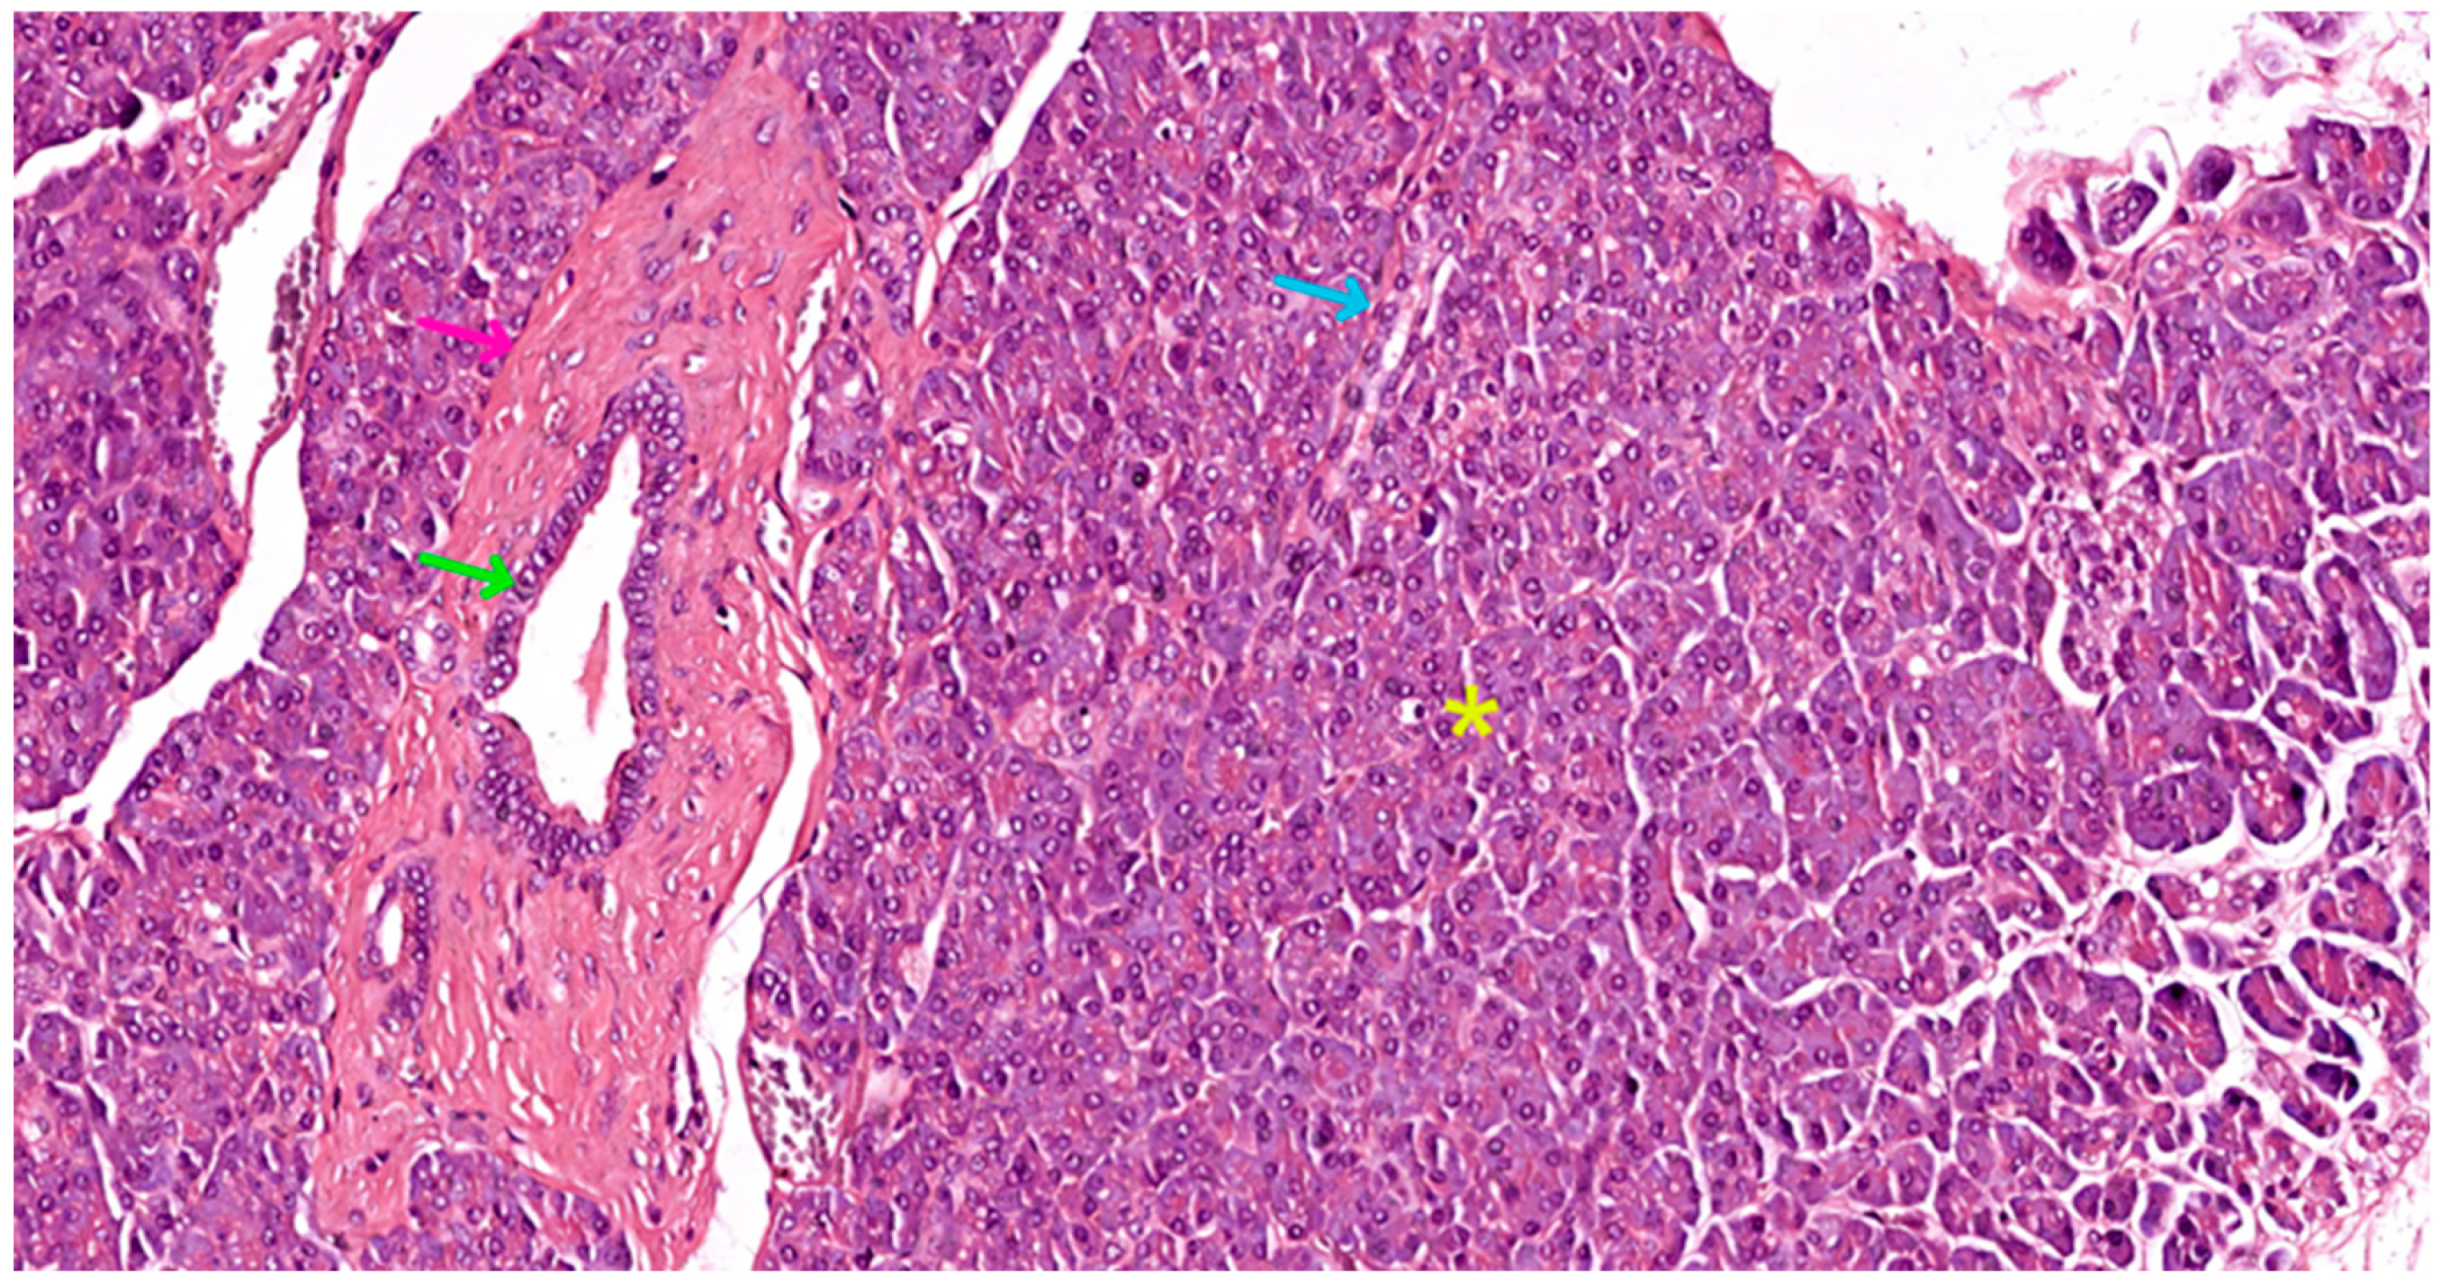

- Centro-acinar cells—delimiting the lumen together with acinar cells; they are small, flattened, or cuboidal in shape; the cytoplasm is pale, and the nucleus is oval; these cells are considered reserve cells for acinar and ductal cells (see Figure 4a).

- Intralobular ducts—represented by intercalated ducts that continue the lumen of the acini and are delimited by simple cuboidal epithelium; intercalated ducts fuse to form proper intralobular ducts, which are larger and delimited by simple cuboidal or columnar epithelium; around these ducts, a loose connective stroma can be observed, with numerous reticulin fibers, yet quantitatively reduced overall; unlike major salivary glands, the exocrine pancreas does not have striated ducts (see Figure 4a,b).

- Interlobular ducts—located in connective trabeculae; they have a wide lumen and are delimited by simple columnar epithelium; they are surrounded by well-represented, dense, irregular connective tissue, which contains fibroblasts and myofibroblasts (see Figure 5).